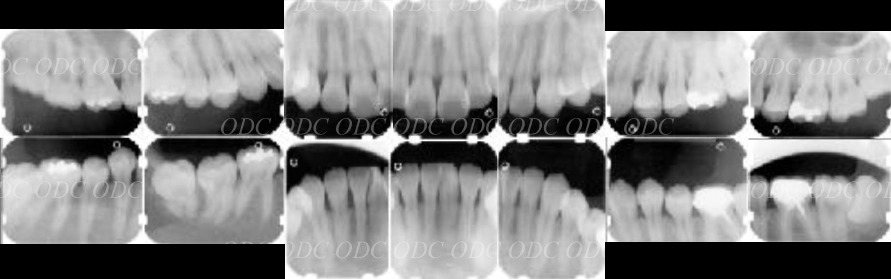

先天性欠損症例

前歯がもともと4本、生えてこなかった症例。

インプラント治療を希望。

顎位(噛み合わせ)を正し、矯正治療にて歯を移動させる。

コンピューターで計画を行い、上部構造に関してもコンピューターにてデザイン。

最終物が装着されるまでに第1のプロビジョナルレストレーション(上段)と第2のプロビジョナルレストレーションを装着。

最終の補綴物が装着された、口腔内写真とレントゲン写真。